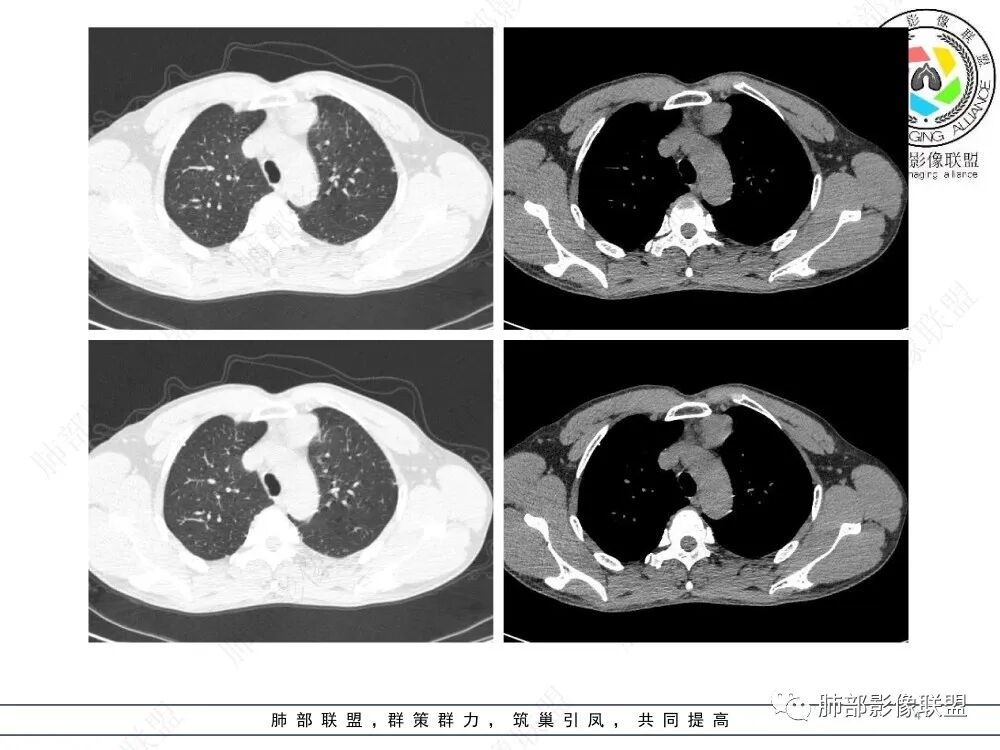

放射小白:男性47岁,前纵隔团块状占位,边界尚清,增强中度强化,内部疑似纤维分隔,常规考虑胸腺瘤可能(A/AB型),鉴别类癌、CD。

瑞欣:中年男性,检验未见明显异常,前纵隔软组织快影,边界清,可见明显强化,首先考虑胸腺瘤,鉴别淋巴瘤,畸胎瘤,生殖细胞瘤。

金豆:晨读:定位前纵隔,膨胀性生长,质地中等,边界清,有浅分叶,中等强化,似乎有裂隙低密度,常规胸腺瘤(B1)。

Yishion:晨读:纵隔占位,偏侧生长,边界清楚,有浅分叶,强化明显,其内似见纤维分隔,常规考虑胸腺瘤(AB型)。

蓝天白云:晨读:47岁男,前纵隔占位,边界清,有浅分叶,中等强化,胸腺瘤(B1)。

宇宙:前纵膈偏左类圆形肿块,边界清晰光整,与大血管脂肪间隙清,密度均匀,轻中度强化,考虑胸腺瘤,A型?鉴别胸腺癌。

玫:男,47岁,咳嗽,咳痰一年,前纵隔软组织密度肿块影,边界清晰,内密度均匀,增强扫描轻度强化,考虑胸腺瘤可能。

周太狼:中年男性,前上纵隔胸腺区软组织团块占位,边界清,增强中度强化,内密度较均匀,常规考虑胸腺瘤。

月亮圆了!:前纵隔包块,边界清,有分叶,密度不均,中等强化,考虑胸腺瘤。

衡妈🇨🇳:中年男性,前纵隔偏左侧实性占位,密度相对均匀,边缘分叶,周围脂肪结构略模糊,增强后动脉期不均匀强化,有低密度区,纤维分隔显示不清。考虑胸腺瘤B1 B2型。

朱伟超:中年男性,前纵膈偏离中线肿块,浅分叶,内有分隔,中等不均匀强化,常规胸腺瘤。

流心明智:男,47,咳嗽、咳痰1年余。胸部CT:前纵膈偏左类圆形肿块,瘤肺界面清晰光整,纵隔侧部分层面絮状影?平扫密度较均匀,增强后轻度强化,内可见宽带及线样低密度分隔。邻近左上肺受压凹陷。考虑胸腺肿瘤,AB型?胸腺Ca?鉴别淋巴瘤、N源性肿瘤、CD等。

1、临床特点:47岁男性,咳嗽咳痰1年余。实验室检查无特殊。

2、影像特点:前纵隔偏左侧软组织影,密度相对均匀,未见明显包膜钙化及实质内钙化,局部边缘浅分叶,周围脂肪间隙密度增高、浑浊,未见侵犯大血管、未见纵隔内淋巴结转移、未见侵犯心包内结构、未见胸膜转移结节、未见肿块沿着纵隔胸膜蔓延,未见胸腔积液。增强后动脉期不均匀强化,未见明显纤维分隔。